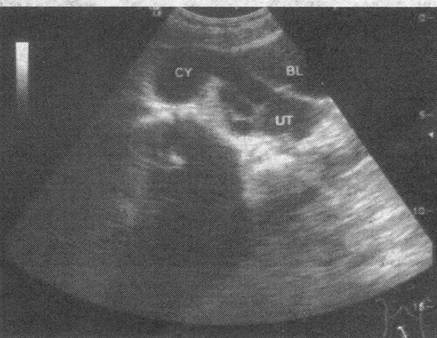

女,27岁,下腹部疼痛数月。体检:右侧附件区增厚、增大,B超检查如图所示,最可能的诊断为(  )。

A.右侧卵巢囊肿

B.右侧输尿管扩张

C.右侧输卵管积液

D.盆腔积液

E.右侧卵巢肿瘤